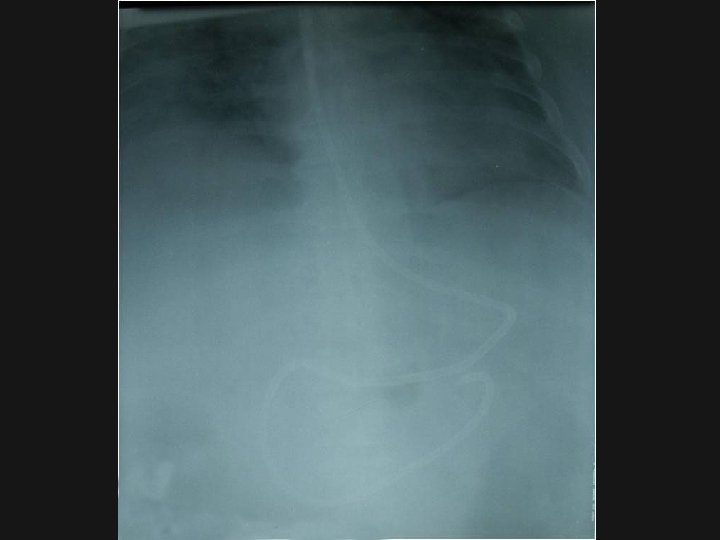

Jejunal Feeding n n n Jejunal feed: via a tube placed Trans-nasally by endoscopy, radiologically, at the bedside. Into the jejunum either at laparotomy or laparoscopy May reduce incidence of aspiration Often increases dose of EN given over NG

Access for PN n n n Usually central line in ICU – keep a clean port if PN may be needed. 5 lumen Short term PN – can have PIC (need a different formula) or PICC Long-term TPN – tunnelled subclavian catheter (Hickman) or subcutaneous port is usually inserted – OBSERVE STRICT ASEPSIS if handling these lines.

Tubes and Lines